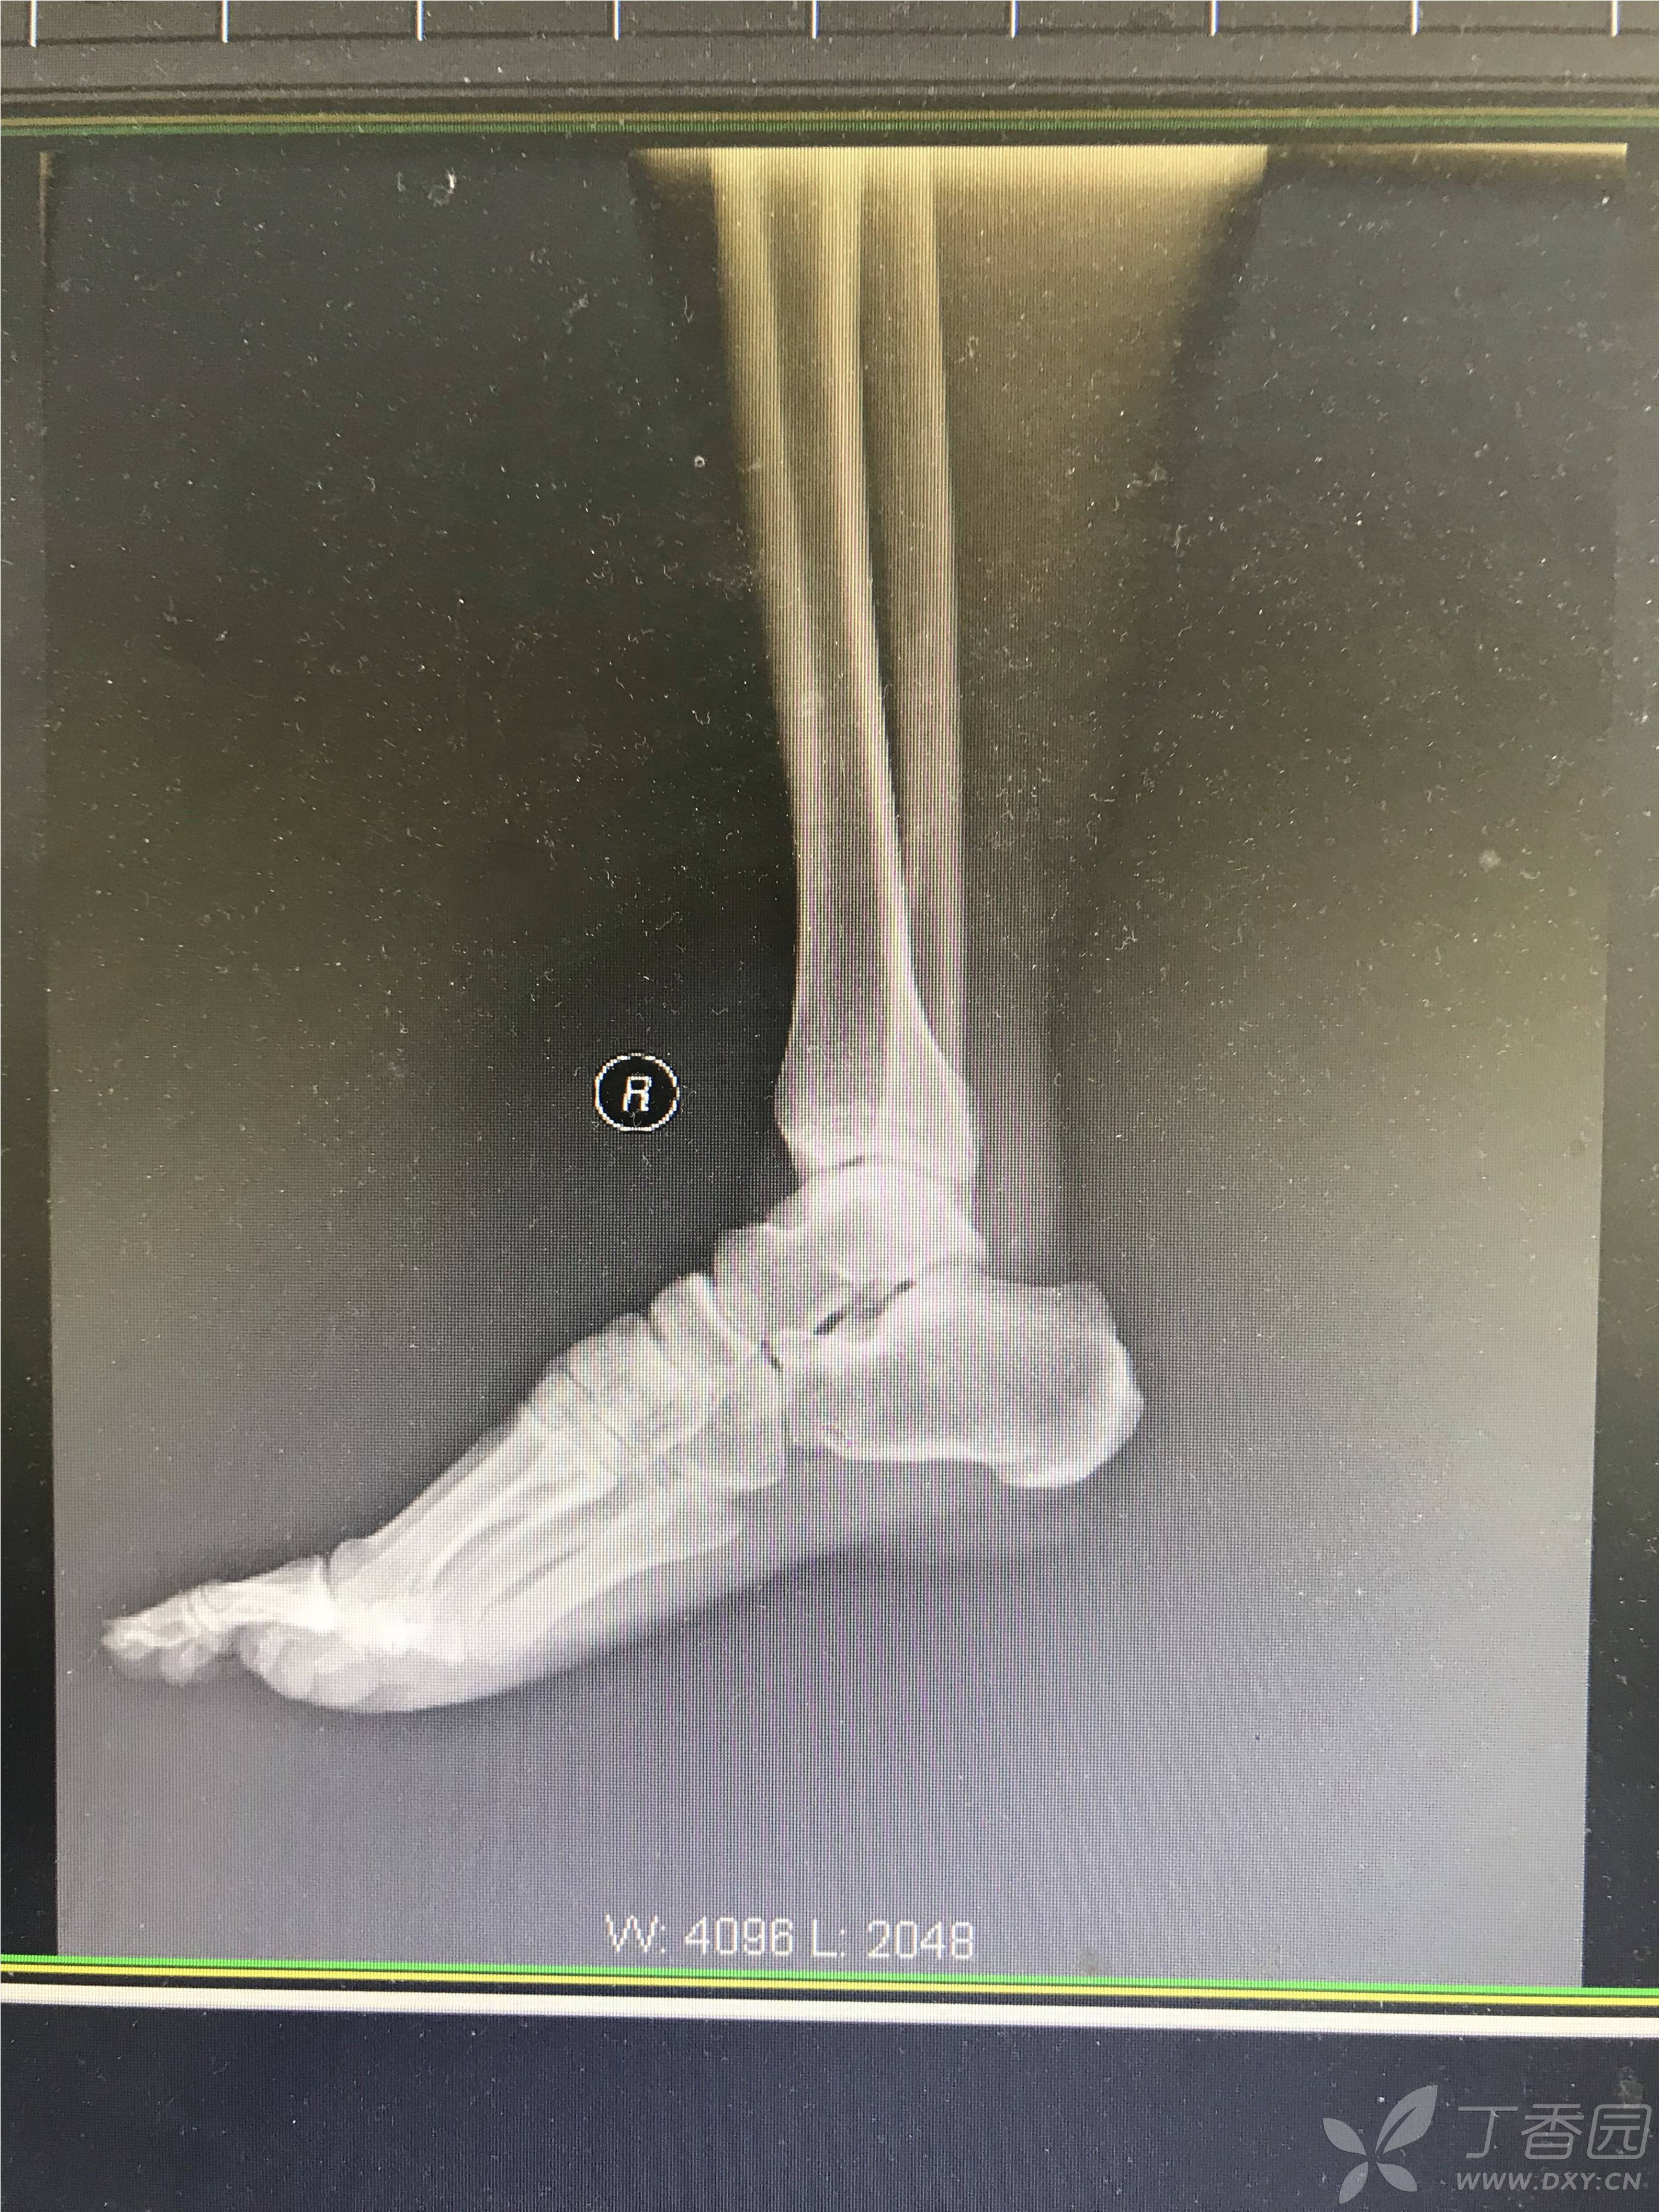

一例罕见的距下关节脱位

图片尺寸3026x4034

图片尺寸3025x4033